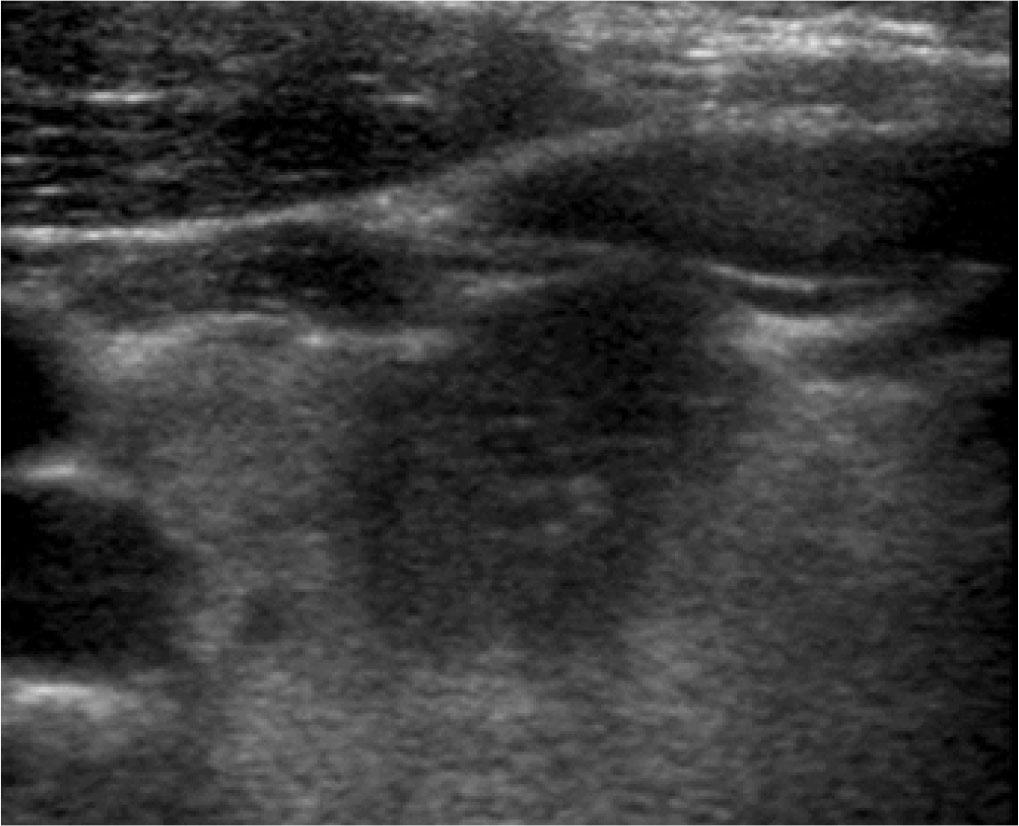

As it turned out, the models obtained the best results when classification decisions were made on the basis of features commonly as associated with increased or reduced risk of malignancy. However, these features were inferred by the Recursive Feature Elimination process. The RFEC formula was used, thanks to which the nodule features most important for the correct classification decision of the models (benign lesion/malignant lesion) were identified. The most significant features for the studied model included irregular margins and solid or almost solid composition of the lesion (>90%). It corresponds to the US features most significantly associated with malignancy as identified by Dobruch-Sobczak et al., irregular margins (Odds Ratio = 13.82), which was also associated with high specificity, and solid or almost solid composition (Odds Ratio = 9.82)(1,12) (Fig. 6).

Thyroid focal lesion: solid composition, hypoechogenicity, irregular margins, irregular shape, and extrathyroidal expansion